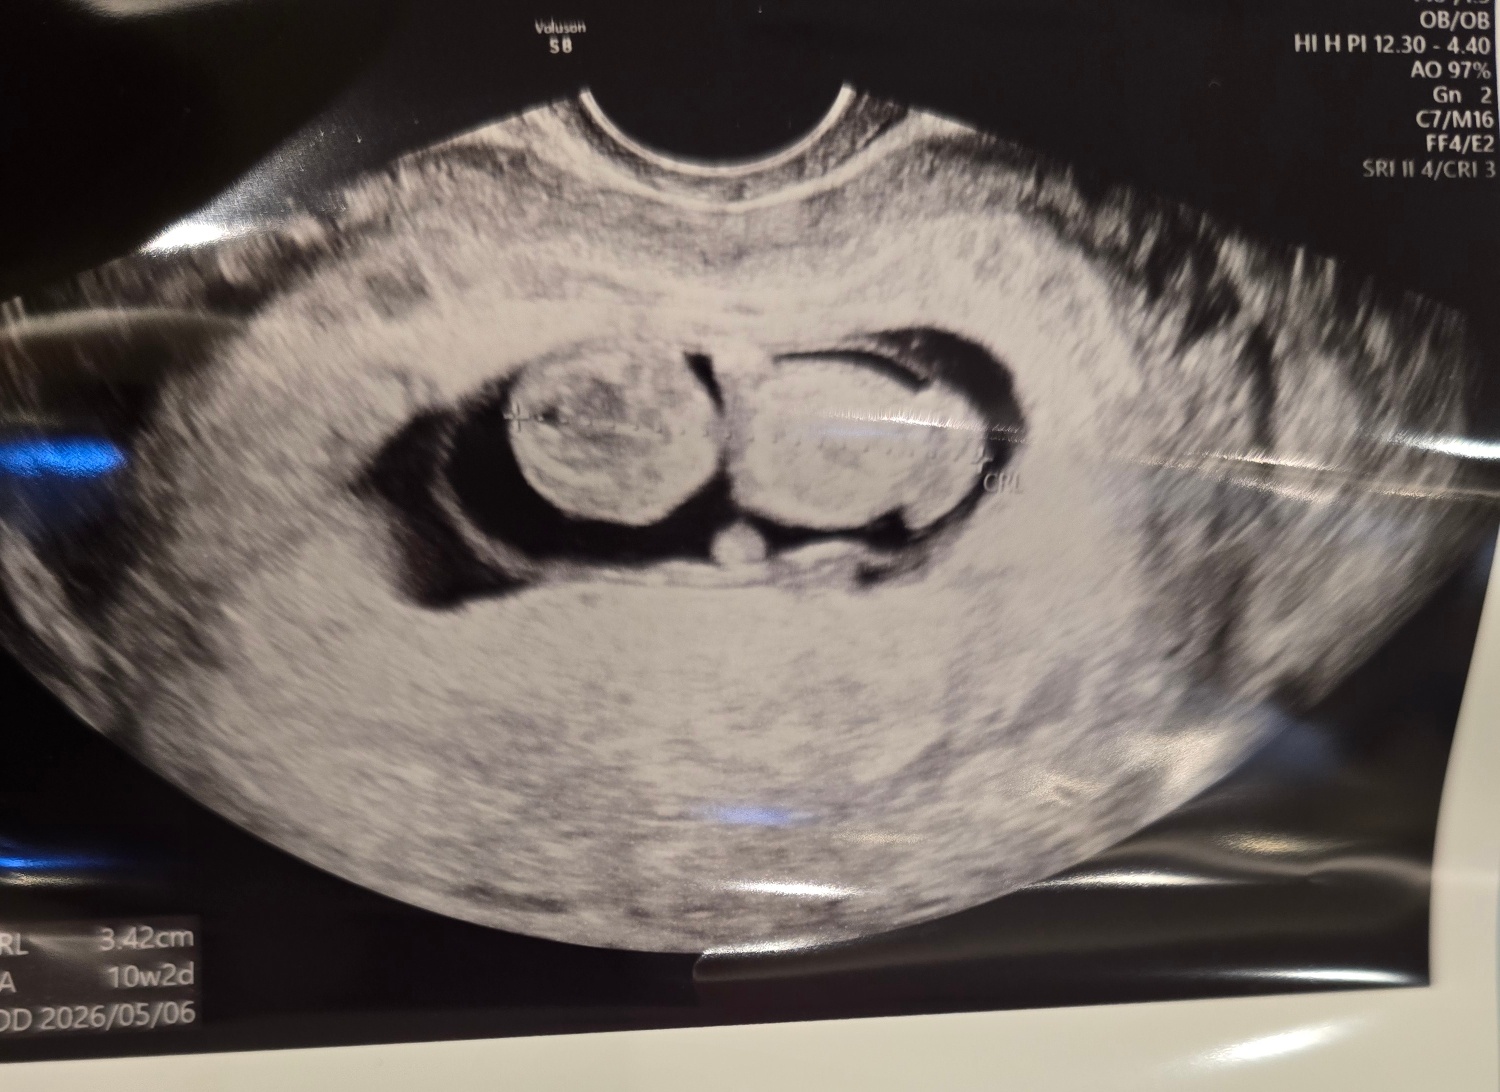

| 가슴 떨리는 임신 이야기를 공유해 주세요. | 인공수정 1차는 어렵다고 해서 기대를 거의 하지 않았는데, 첫 검사에서 아기를 만났을 때 마음이 벅차오를 만큼 설렜습니다. “정말 아기가 온 걸까?” 하는 놀라움과 기쁨이 한꺼번에 밀려왔어요. |

| 치료 도중 느꼈던 가장 기뻤던 순간과 절망적인 것들은 무엇인가요? 잊지 못할 경험이 있나요? | 가장 기뻤던 순간은 인공수정 후 처음으로 검사를 받고 임신 소식을 들었던 바로 그날입니다. |